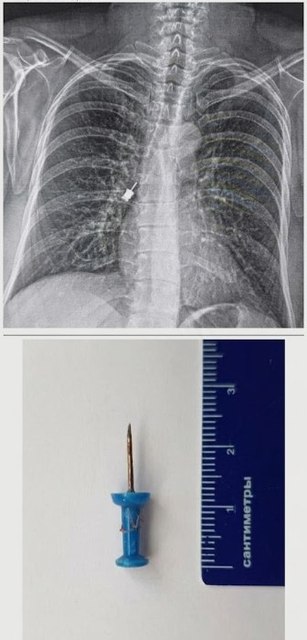

Канцелярська кнопка у підлітка: Через необережність кнопка потрапила до дихальних шляхів. Раптовий кашель став сигналом для негайної госпіталізації. У нашому центрі предмет було оперативно видалено, підліток пройшов повний курс лікування та вже повернувся додому.